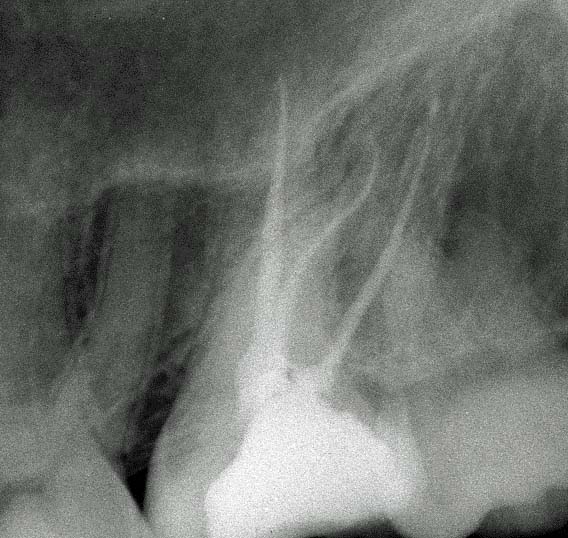

Apertura della corona fino ad arrivare alla camera pulpare (tale trattamento viene eseguito tramite anestesia locale). Si rimuove la polpa e si cercano i canali radicolari del dente, una volta trovati si estirpano i nervi. Si allargano e si puliscono i canali del dente, (tramite strumenti al Nichel titanio o strumenti manuali) prendendo anticipatamente le misure dei canali (per non uscire oltre apice). Si disinfettano i canali e si eseguono vari lavaggi tra un passaggio e un altro per elimininare il fango dentinale. Il medico a questo punto verifica la possibilità di chiudere definivamente i canali o lasciare il dente in prova, inserirendo nei canali un disinfettante e eseguendo una chiusura provvisoria. Al momento di chiudere il dente definivamente, questo viene preparato rieseguendo le misure dei canali da chiudere ed usando per la stessa lunghezza del canale, un cono di guttaperga del diametro necessario. Si scalda il cono in guttaperga e si inserisce nel canale. Durante il trattamento endodondico vengono effettuati una serie di esami radiografici per verificare i risultati, le lunghezze, la forma dei canali.

L'esame radiografico, fondamentale per porre diagnosi in odontoiatria, in endodonzia è irrinunciabile perché è l'unico strumento che ci permette di "vedere" all'interno della radice del dente, è quindi molto importante la possibilità di effettuare lastre con apparecchiature digitali che emettono un quarto della dose di raggi emessa da un radiografico tradizionale e che permettono di conservare la radiografia endorale in una cartella informatica del paziente senza possibili alterazioni nel tempo.